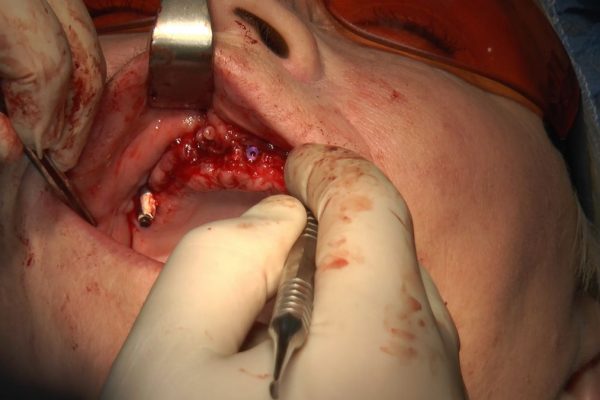

W ostatni weekend czerwca 2018 roku kursanci II Sezonu Preludium Implantologii odbyli piątą, finałową sesję, która w całości podporządkowana była praktyce. W ciągu dwóch dni zabiegowych Lekarze uczestniczący w szkoleniu przeprowadzili szereg zabiegów pod kierunkiem dr n.med. Violetty Szycik. Wszczepili 17 implantów oraz przeprowadzili ekstrakcje i zabiegi regeneracyjne kości. Zabiegi były wykonywane także w sedacji dożylnej z udziałem specjalisty anestezjologii i intensywnej terapii dr Jolanty Grzybowskiej. Preludium implantologii to nowy program edukacyjny dla adeptów implantologii stomatologicznej, którego celem jest wprowadzenie do implantologii poprzez pozyskanie wiedzy w szerokim zakresie i uwzględnieniem szczegółów mających decydujące znaczenie dla powodzenia leczenia implantologicznego. Ale tak jak wszystkie szkolenia w Instytucie Vivadental, w tym wiodące Practiculum Implantologii, zorientowane jest na praktyce i samodzielnym wykonywaniu zabiegów pod kierunkiem Mentora. To najlepsza edukacja w medycynie zabiegowej, a zarazem najlepszy start do implantologii.